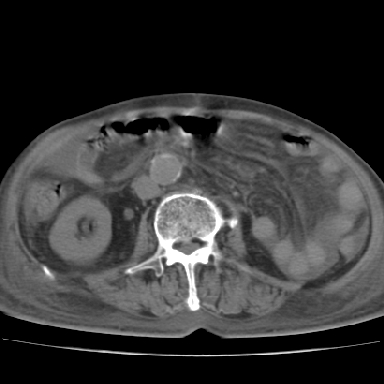

以下是引用qian在2006-12-4 19:11:00的发言:[br]胸腔和腹腔内均见有液性影,肝上极包膜下有一较大椭圆形低密度影,密度均匀,边缘清晰,结合病史考虑术后肝脓肿并胸腹腔积液。

以下是引用chry3在2006-12-4 21:05:00的发言:[br]应该往上扫几层,我考虑膈下脓肿。[br]大家考虑:胃部手术怎会造成肝内脓肿,隔下脓肿到是会造成的

以下是引用dyqct在2006-12-4 19:54:00的发言:[br]考虑:1、肝包膜下脓肿;[br] 2、少量腹水;[br] 3、右侧少量胸膜腔积液。